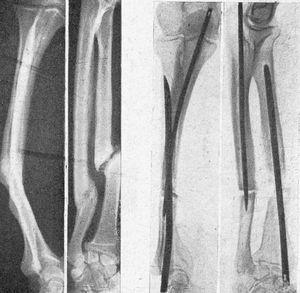

Figura 1. Fractura tercio superior fémur transversal, reciente, enclavijamiento cerrado. La misma, una vez enclavijada; correcta reducción e inmovilización que permiten la marcha sin ningún otro procedimiento secundario de inmovilización.

Figura 2. Fractura transversal tercio medio tibia, sin desviación, peroné íntegro, enclavijamiento cerrado; fue uno de los primeros casos tratados, y a los tres meses reanudaba el trabajo; un solo clavo mantuvo una perfecta inmovilización.

Figura 3. Fractura tercio medio tibia y peroné; enclavijamiento cerrado con un solo clavo; un tercer fragmento impide la exacta coaptación de fragmentos, obteniéndose, no obstante, una buena consolidación con predominio de callo periostal; se aprecia en la parte superior el orificio de la trepanación de entrada del clavo.